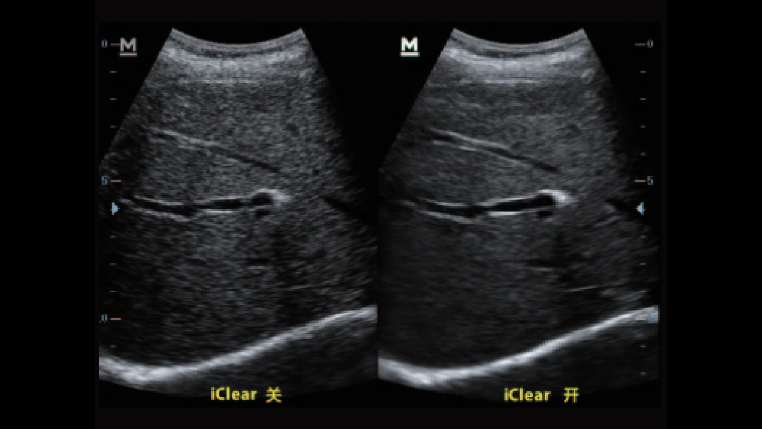

iClear斑点噪声抑制

自动均衡的噪声抑制技术能够识别并增强有效的诊断信息,抑制噪声干扰,使人体组织结构更清晰